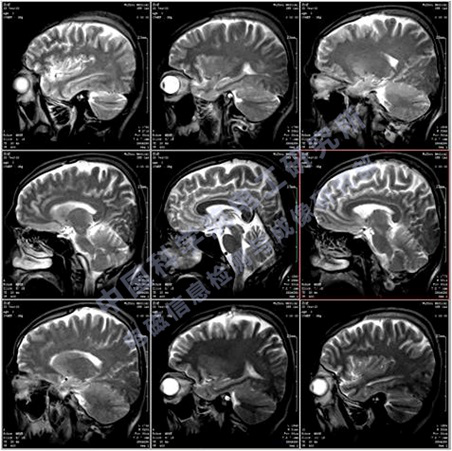

移動式POCI磁共振成像儀屬于POCI(point of care imaging)成像裝備,也就是即時監護成像,包括但不限于:神經內科和神經外科的腦監護成像、新生兒腦監護、口腔醫學以及運動損傷監護等,主要用于各類相關臨床醫院、科研機構、研究型醫院,用于臨床診斷和疾病的動物模型研究、認知研究、新藥研發等。我們研發的移動式POCI磁共振成像儀,采用了最新的輕量化永磁磁體技術和高效率的矩陣梯度技術,使得整機具有更高的磁場強度、更低的使用成本、更好的成像效果和適用性。目前國內MRI裝機量超過了11000臺,而移動式POCI磁共振成像儀目前國內外還沒有成熟的產品。預計將來移動式POCI磁共振成像儀的需求量接近全身MRI設備的需求,其總市場價值約有150億元,因此移動式POCI磁共振成像儀具有良好的市場前景和經濟效益。